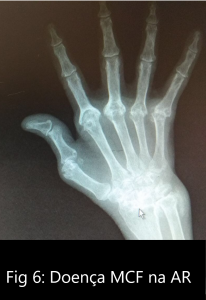

As deformidades das MCFs tem origem na sinovite articular que provoca laxidez capsulo-articular, seguida de lesão e posterior destruição osteo-cartilagínea) (ver figura 6).